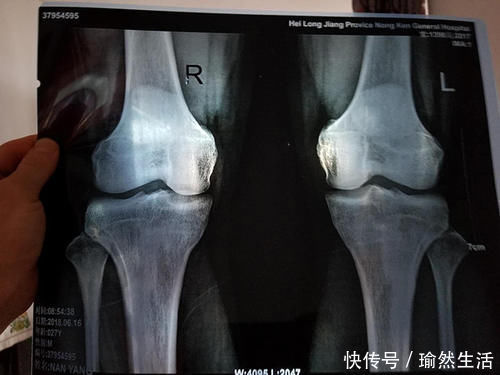

虽然普遍来说,男性到25岁之前,女性到23岁之前都还有长高的可能性。

但每个人的身体状况不一样,有的人的骨骼线可能会闭合得比较早一些,所以家长要知道孩子什么时候会停止长高,并抓住这最后的机会进行“全力冲刺”!

正常情况下,骨骼线即将闭合,也就是孩子在停止长身高之前,身体都会发出以下三个信号:

所以,当他进入青春期的时候,家长应该带他去医院做一次全面的体检,看看是否有性早熟、发育过快的情况,并且根据检查结果及时调整“长身高计划”。